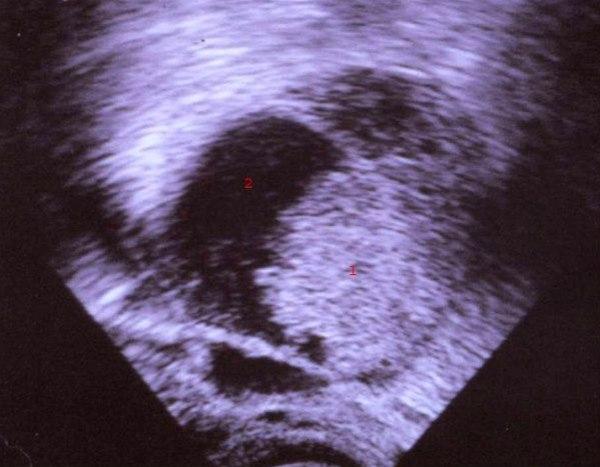

Endometroid adenocarcinom

1. Solid tumormasse

2. Uteruscavitet